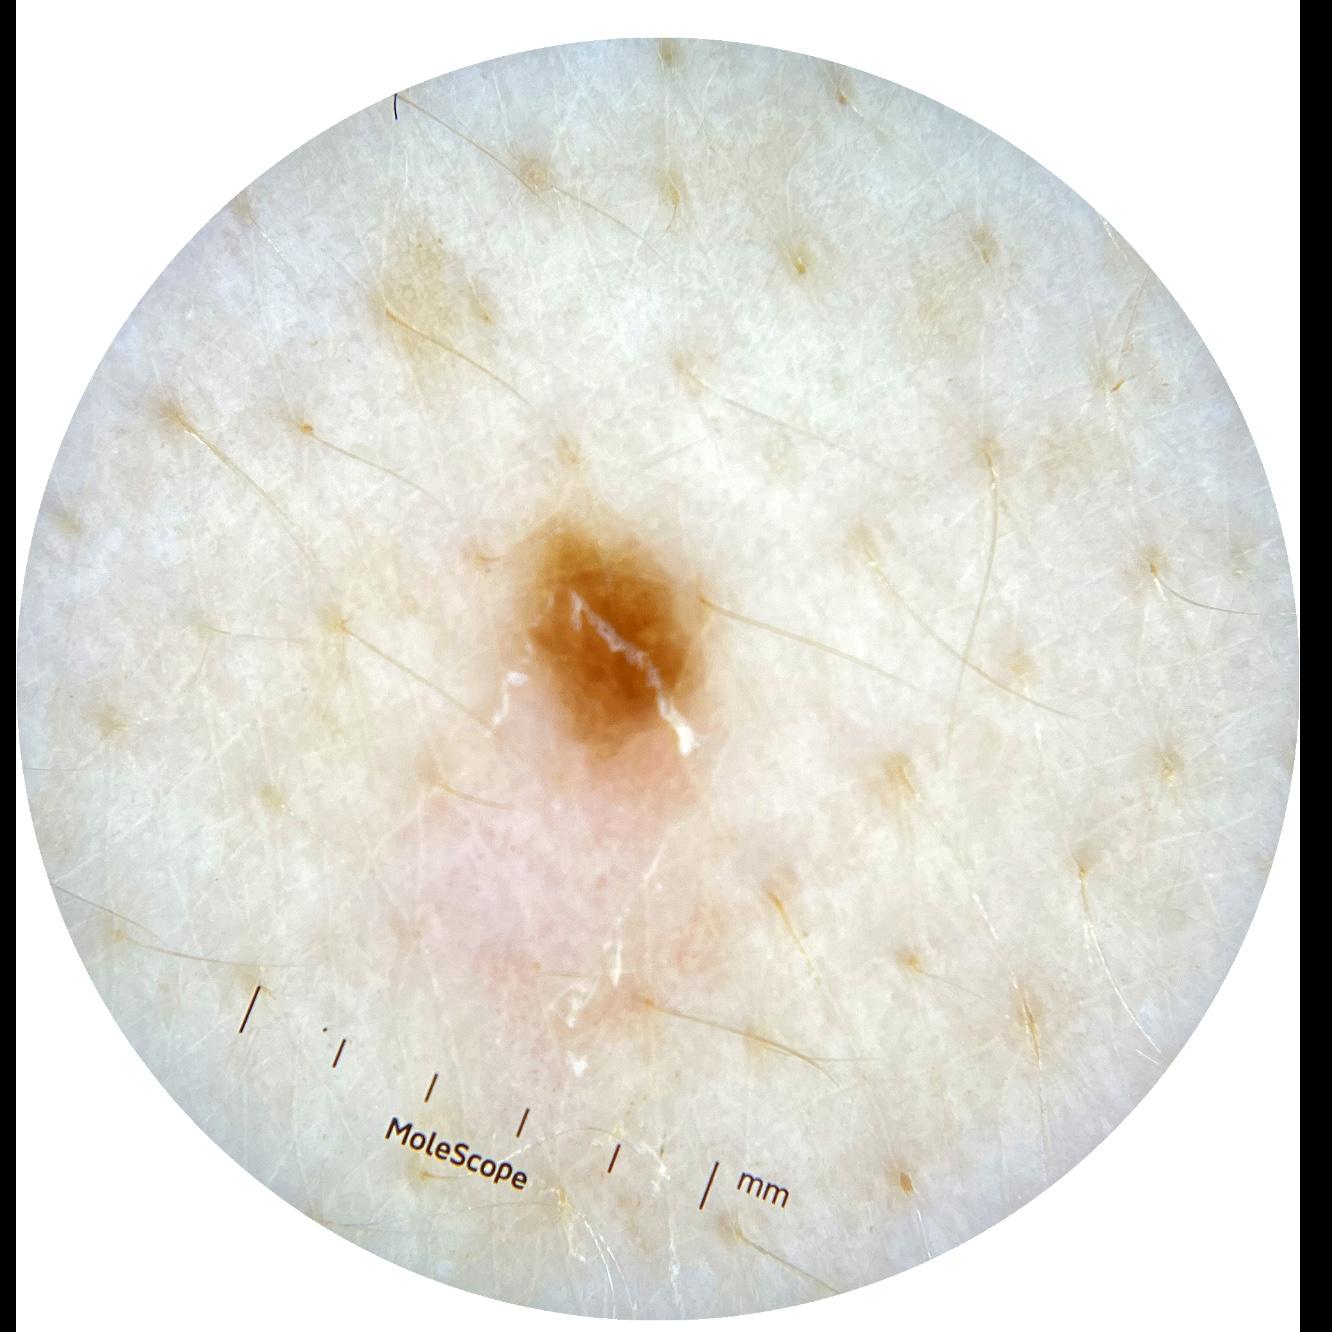

ISIC_0301375

1986 x 1986

acquisition_day 331

age_approx 35

anatom_site_1 Trunk

anatom_site_2 Anterior trunk

anatom_site_general anterior torso

diagnosis_1 Benign

diagnosis_confirm_type single image expert consensus

image_type dermoscopic